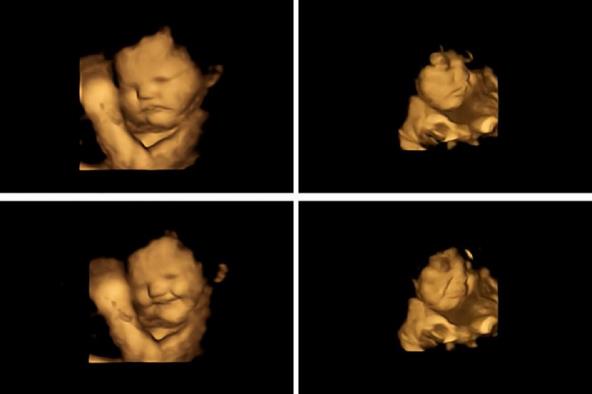

Ovako izgleda nerođena beba čija mama je jela šargarepu:

beba-smeje-ultrazvuk.jpg

Beba se smeje na ultrazvuku Foto: Fetal and Neonatal Research Lab; Durham University/screensh

A ovako ona koja je okusila kelj:

beba-ultrazvuk-mršti.jpg

Beba se mršti na ultrazvuku Foto: Durham University. / Ferrari/screenshot

Nakon pregleda obavljena je analiza svakog snimljenog kadra izraza lica fetusa, uključujući i kombinacije grimasa koje su izgledale kao plač ili smejanje. Napravljeno je više od 180 ultrazvučnih snimaka na 99 fetusa, koji su skenirani u 32. i 36. nedelji trudnoće.

Plačni izrazi lica bili su dva puta češći kada su majke konzumirale kapsule sa keljom u poređenju sa fetusima čije su majke uzimale kapsule sa šargarepom ili nisu uopšte uzimale kapsule.